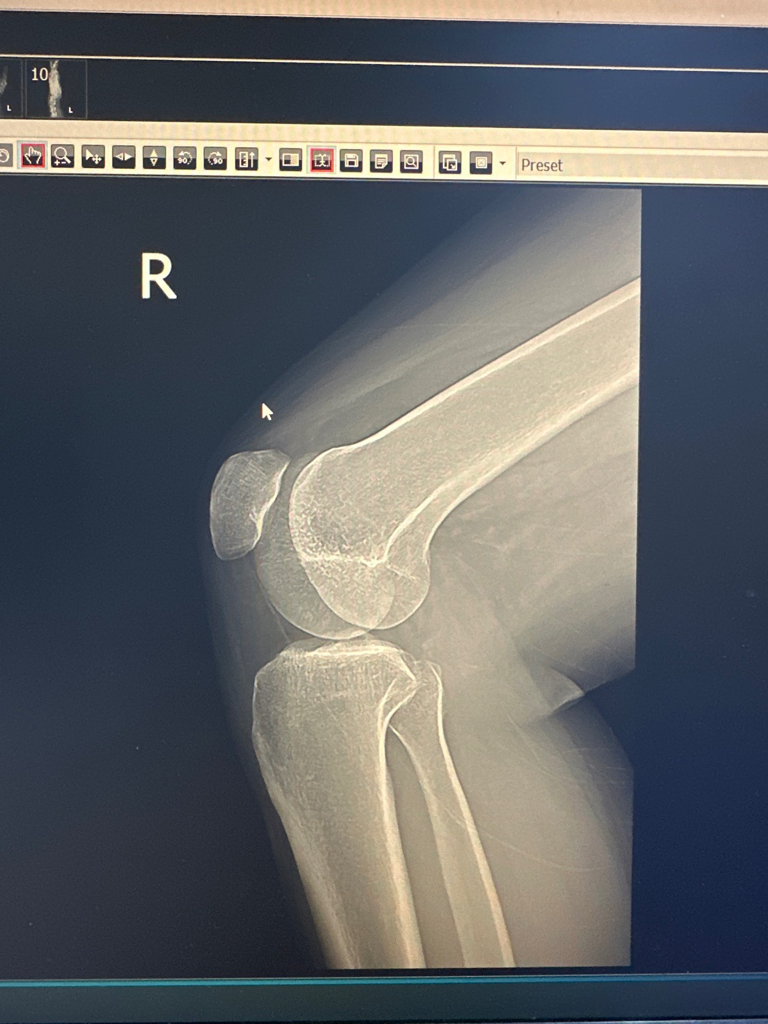

전공이 아니라 말씀드리기가 조심스럽지만 왼쪽 무릎 위쪽의 대퇴골에 덩이로 추정되는 것이 보이고 있어 추가검사를 요하는 것 같습니다. 골종양을 확인해야만 하는 상황이라 보입니다만 강력히 권한 정도가 아니라면 악성을 의심하시는 것 같지는 않습니다.